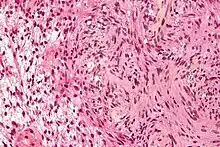

Pathology

The so-called acoustic neuroma of NF2 is in fact a schwannoma of the nervus vestibularis, or vestibular schwannoma. The misnomer of acoustic neuroma is still often used. The vestibular schwannomas grow slowly at the inner entrance of the internal auditory meatus (meatus acousticus internus). They derive from the nerve sheaths of the upper part of the nervus vestibularis in the region between the central and peripheral myelin (Obersteiner-Redlich-Zone) within the area of the porus acousticus, 1 cm from the brainstem.